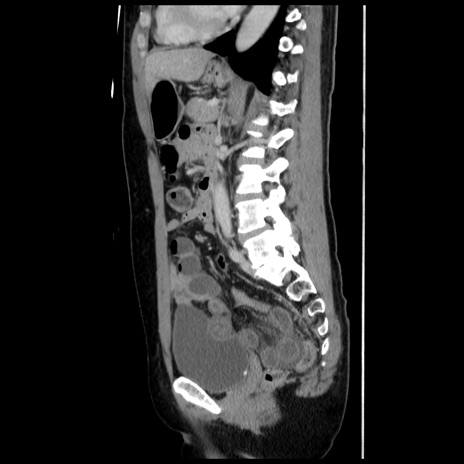

冠状断像